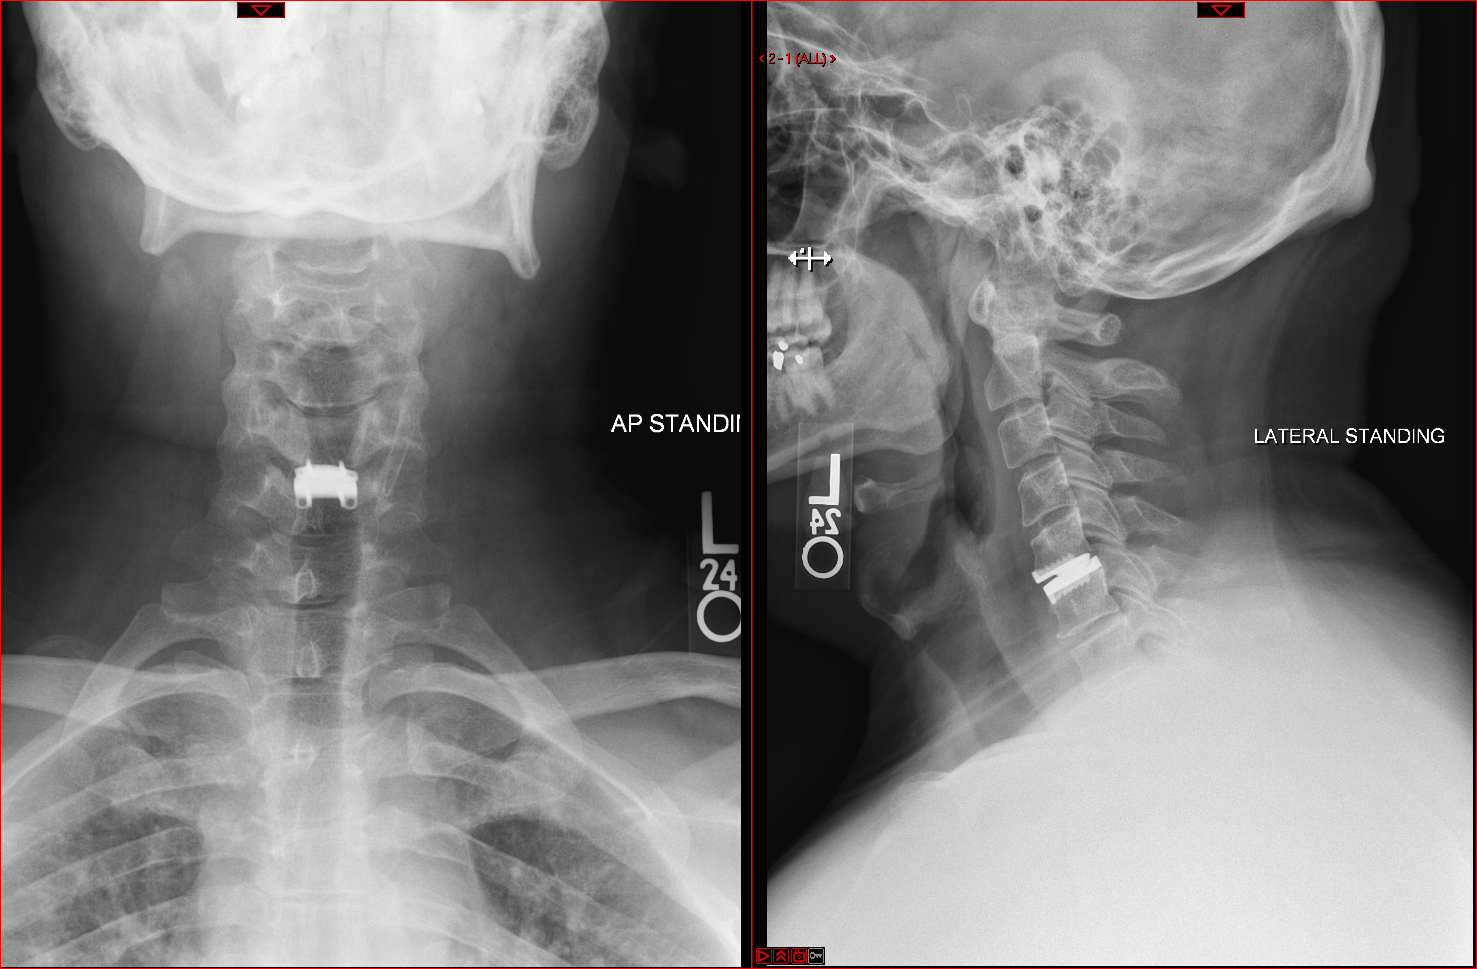

lateral view of spine with disc replacement

By contrast, cervical disc replacement preserves range of motion, and it is also less likely to cause adjacent segment degeneration. There is no need for a cervical collar during recuperation, and patients can return to their routine quickly. Although relatively new in the United States, this procedure has been performed in Europe for more than 20 years.

Furthermore, disc replacement is also technically challenging. The disc must be completely removed, bone spurs eliminated and the artificial disc placed exactly. It is a procedure that requires extensive training, which Li received during a spine surgery fellowship with Daniel Riew, MD, one of the world’s foremost authorities on cervical disc replacement.